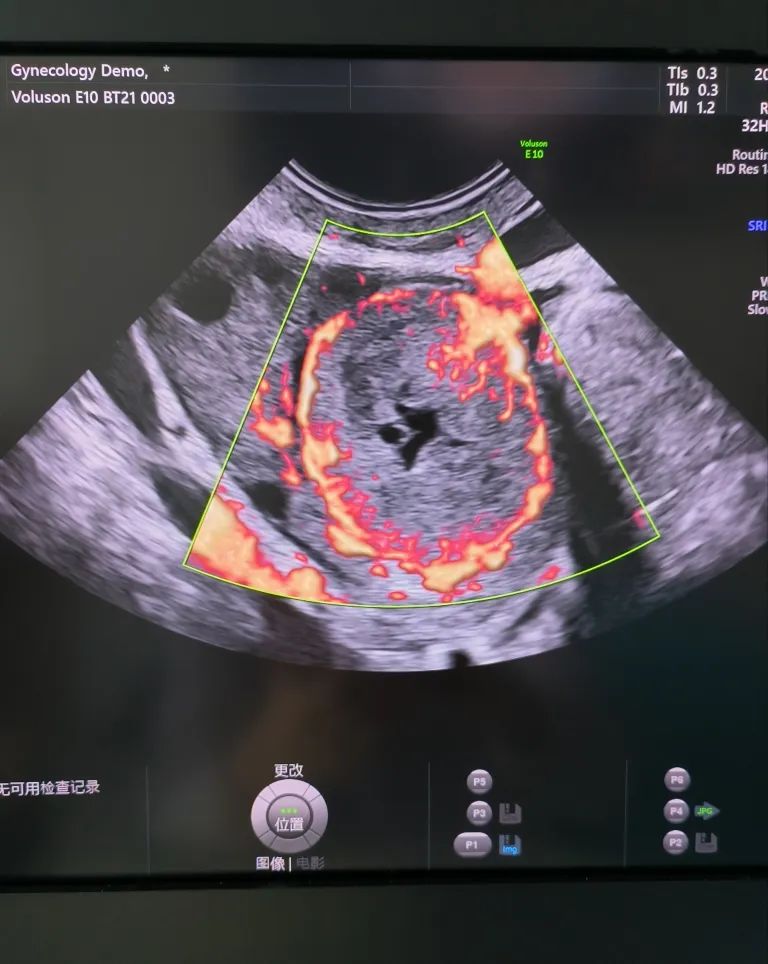

經(jīng)陰道超聲是在陰道超聲探頭上套上避孕套,將探頭伸入陰道進(jìn)行檢查。由于探頭位置接近子宮和卵巢,圖像更清晰,檢查結(jié)果更準(zhǔn)確。而且不需要憋尿,相對(duì)節(jié)省時(shí)間。所以現(xiàn)在大部分醫(yī)院對(duì)有性生活史的婦女更愿意開展經(jīng)陰道超聲檢查。